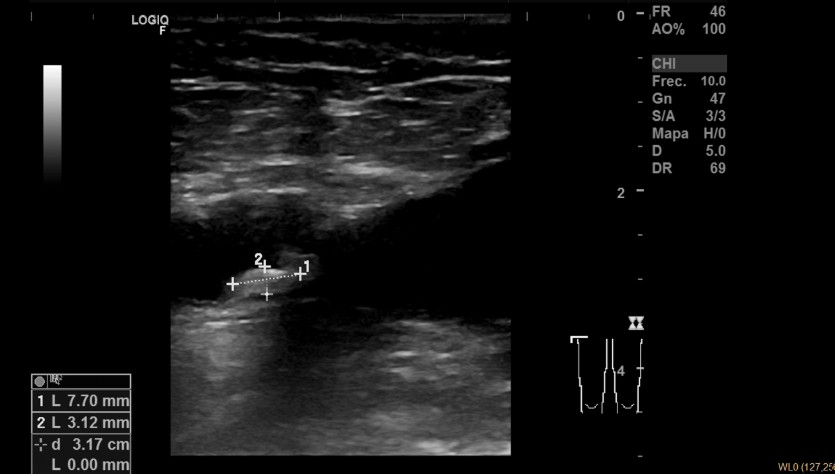

Descripción de los hallazgos ecográficos y las imágenes más relevantes para la resolución del caso: Ecografía multivaso: Placa translúcida de 1,97 x 8 mm en bulbo de carótida derecha, placa translúcida de 6,56 x 2,11 mm en carótida izquierda, placa hiperecogénica de 7,7 x 3,12 mm en femoral derecha. Aorta normal.